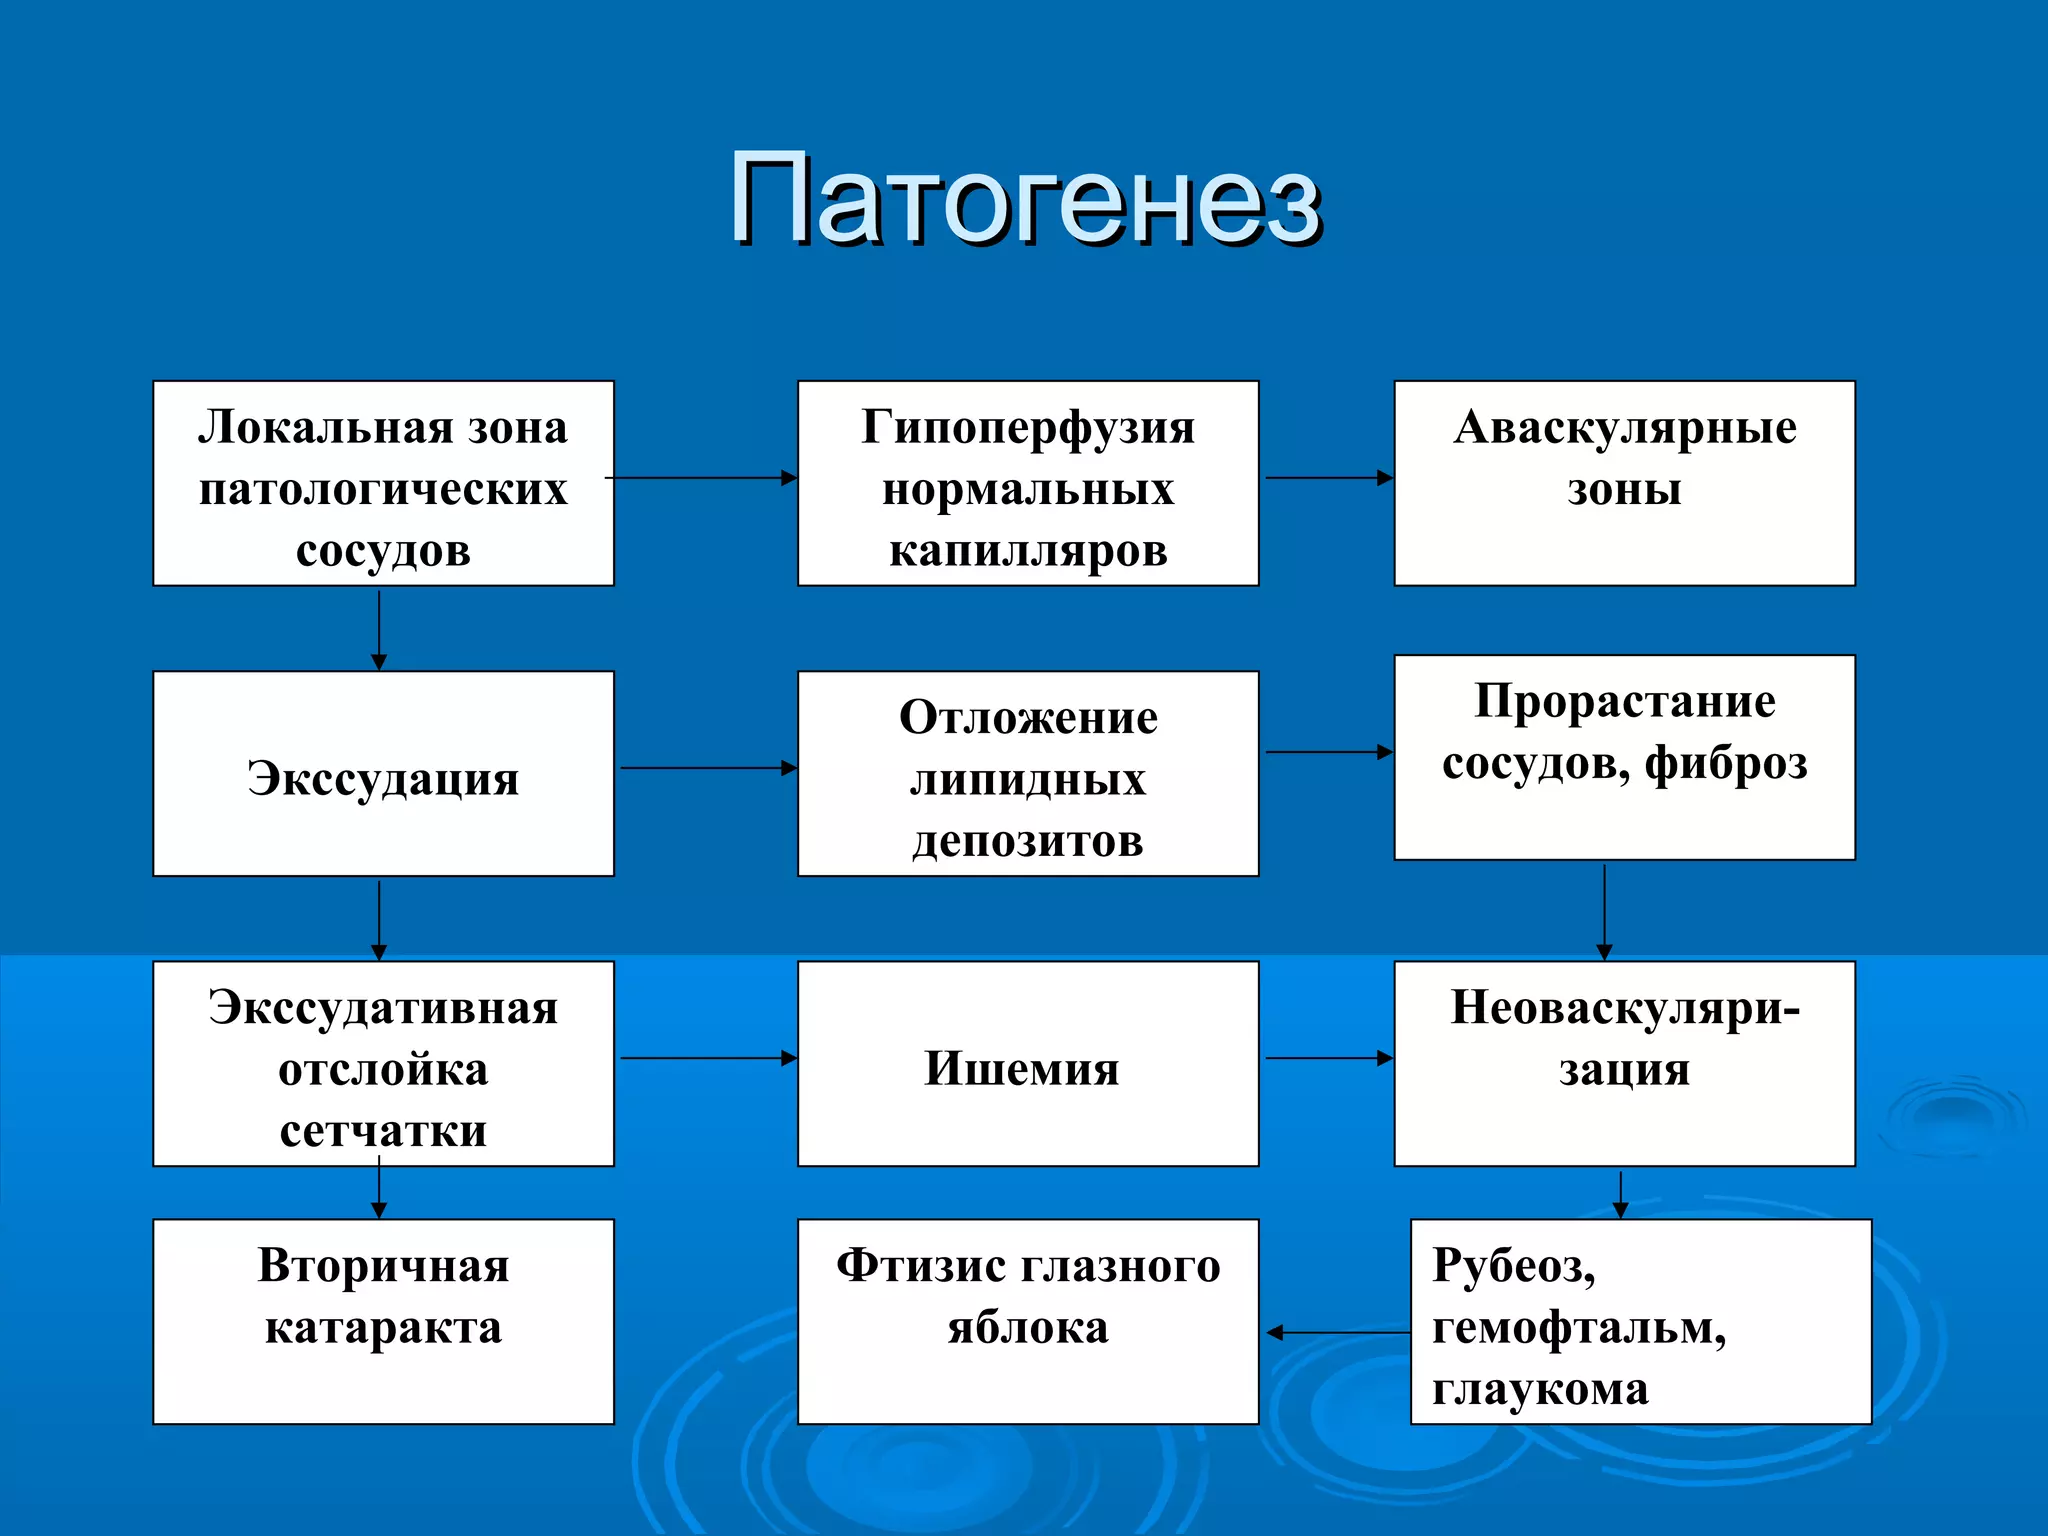

Болезнь Коатса - это идеопатическое заболевание, характеризующееся полиморфными изменениями сосудов сетчатки с массивной экссудацией, чаще всего у детей и подростков, с преобладанием среди мальчиков. Эпидемиология показывает, что заболевание проявляется, как правило, в возрасте 8-16 лет, но возможно его обнаружение и у взрослых. Основные проявления включают ретинальные аномалии, субретинальную экссудацию и постепенно прогрессирующую потерю зрения.